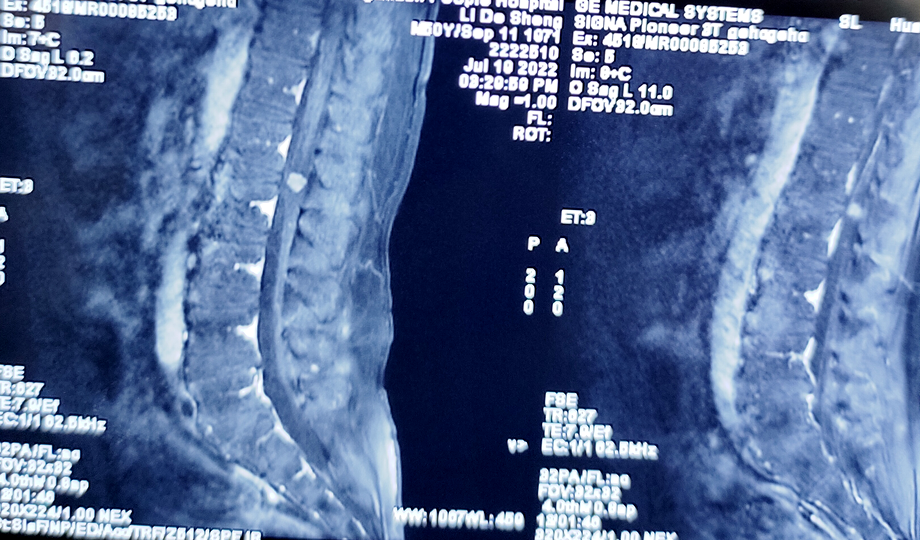

脊髓肿瘤术中

切除前

切除后

脊髓肿瘤术前

脊髓肿瘤术后